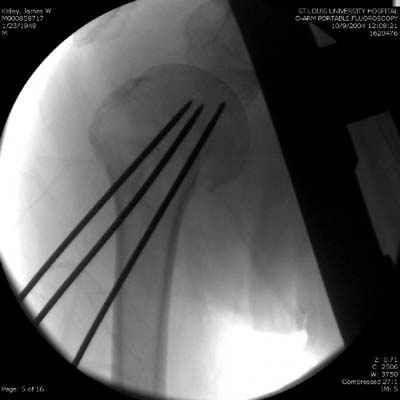

Женя, а как ты водишь спицы, в смысле, как делаешь входное отверстие, и как в него проводишь V-спицу? А то о дна из спиц, та, у которой не дошла до головки одна палочка буквы V, как-то выглядит на рентгенограмме, как будто или через очень большое отверстие введена, или каждая половинка через отдельные отверстия.

Мне кажется, проблема в том, что не все концы спиц зашли в головку, и зашедшие - недостаточно далеко прошли.

Спицы провожу по передней и задней поверхностям плечевой кости через 4,5 мм отверстия на разных уровнях.

Идеей презентации случая была демонстрация важности постоп Рг - хотя казалось бы все было сделано под флюороскопическим контролем и интраоперационно подозрений на нестабильность не возникло, а такая вот

неожиданность...

Уточни - обе части буквы V вводишь в одно отверстие? А то по снимкам выглядит, что в разные.

V-спица проводится через 4,5 мм отверстие. Видимо, из-за разной длины вторая половина спицы *пролетела* мимо отверстия, что и привело к вторичному смещению костных фрагментов.